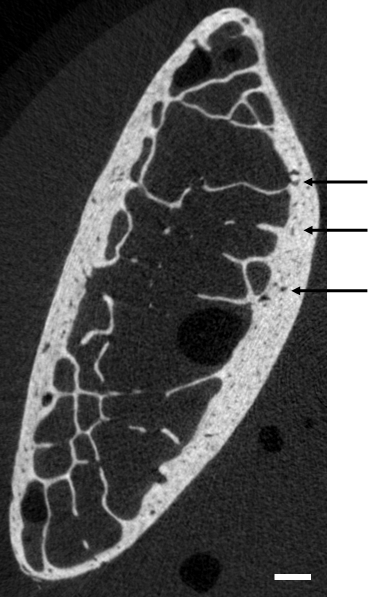

Rib fractures are a good indicator of the severity of an impact to the thorax as the protection to the internal organs such as the lungs and the heart is greatly reduced with the increasing number of fractured ribs (abbreviated injury scale, AAAM (2008)). Injury mechanisms for the ribs and the whole rib cage have been widely studied, either through experiments (Kent et al., 2004; Vezin and Berthet, 2009; Kuppa and Eppinger, 1998; Trosseille et al., 2008; Hallman et al., 2010; Petitjean et al., 2003; Lessley et al., 2010b) or computational simulations (Murakami et al., 2006; Lizée et al., 1998; Song et al., 2009; Robin, 2001; Vezin and Verriest, 2005; Shigeta et al., 2009; Kimpara et al., 2005; Plank and Eppinger, 1989; Ruan et al., 2003; Li et al., 2010a, b; Kimpara et al., 2006) to determine injury mechanisms and thresholds under diverse load conditions. A significant milestone was achieved in the characterization of the strength of the thorax by accounting for the geometrical variations in the rib cage and the rib themselves, and for the effects of biological variations such as aging (Berthet et al., 2005; Ito et al., 2009; Gayzik et al., 2008; Kent et al., 2004). Ribs were shown to have a complex geometry that includes variation in the shape of the cross-section along the rib axis (Kindig, 2009), an increase of the twist from the posterior to the anterior aspect (Mohr et al., 2007), as well as a non uniform distribution of the cortical thickness (Choi and Lee, 2009). In a recent study, Li et al. (2010b) investigated the sensitivity of the rib structural response obtained from a computational model to (a) the accuracy in the reconstruction of the rib (quantified by the mesh density), (b) the cortical thickness distribution and (c) the material properties. The response of the rib finite element model was found to be little sensitive to the choice of material properties, whereas clear trends were observed in the effect of the mesh density and cortical thickness distribution. In finite element modeling, the cortical shell is defined as a continuum made of pure cortical bone (Li et al., 2011). However, rib cortical bone has voids and is not homogeneous (figure 1), and therefore the bone material properties documented for homogeneous bone are likely to inadequately represent the mechanical behavior of rib cortical bone.

Refer to caption

Figure 1: Cross-section of the left 6th from the antero-lateral aspect, from micro-computed tomography. The arrows indicate voids. The bar scale is 1 mm long.